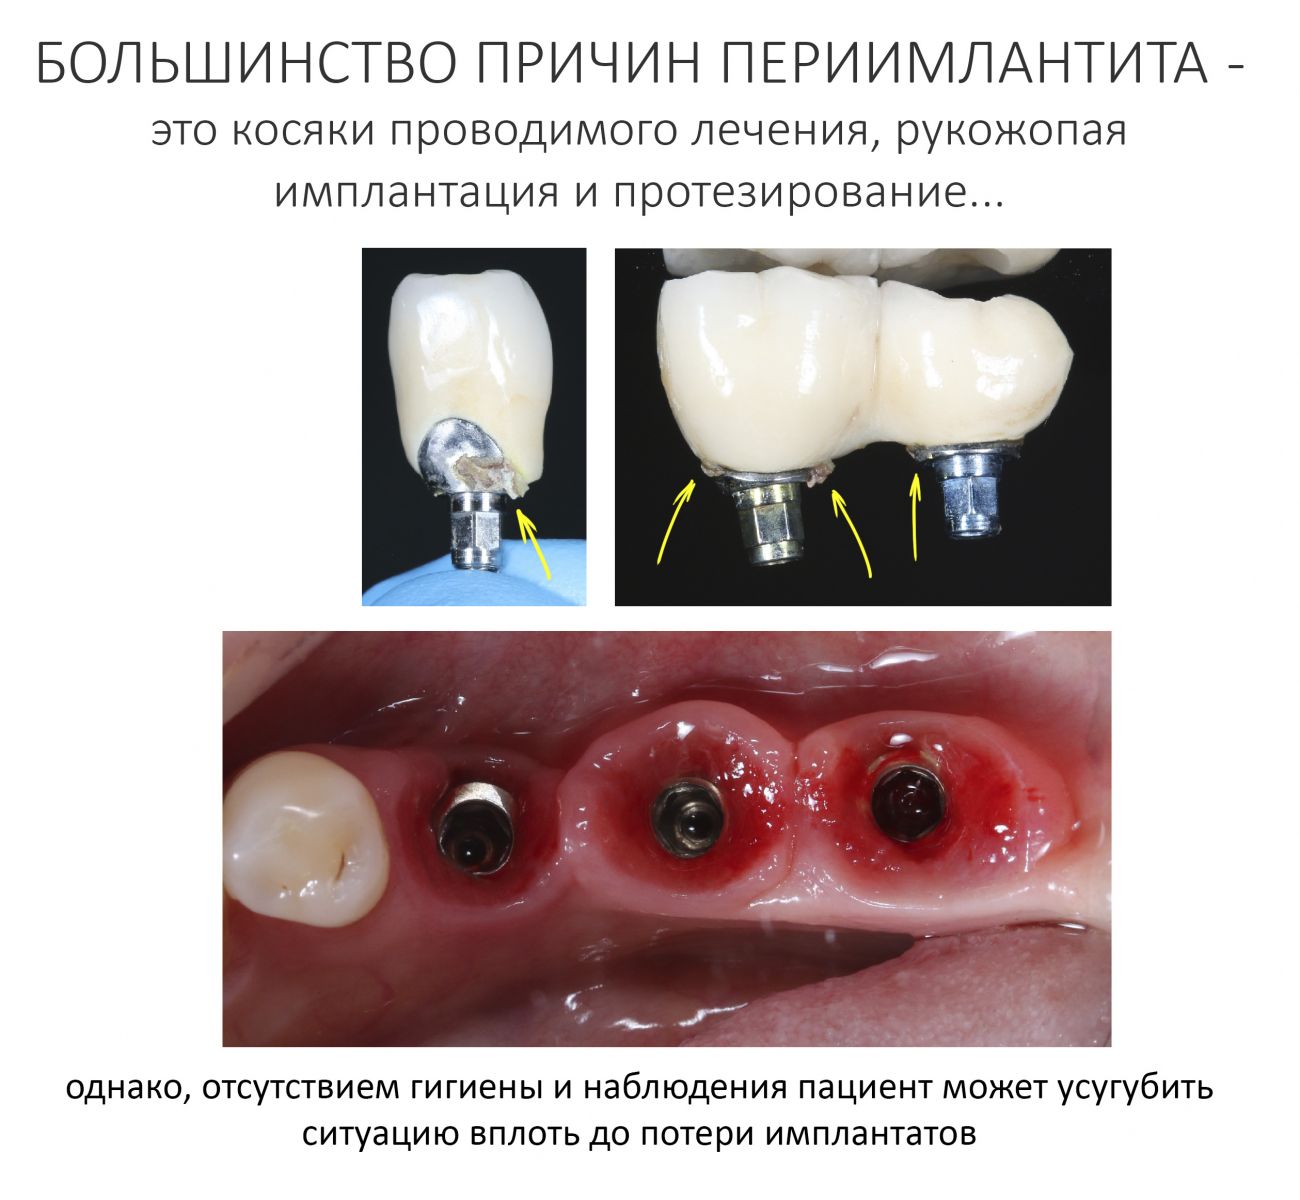

Кстати, о периимплантитах. Написано о них много, даже очень много. Это хроническое заболевание, входе которого воспаляется слизистая оболочка в области имплантата, из-за воспаления разрушается костная ткань вокруг него, образуя характерную «периимплантитную воронку», инфицируется поверхность имплантата и т. д. Чем раньше он выявлен, тем проще его победить. И наоборот.

Как я отметил выше, 99% утрат уже интегрированных и протезированных имплантатов происходит именно по причине запущенного периимплантита, когда его лечение становится нецелесообразным.

Ведущим фактором в развитии периимплантита является микрофлора полости рта. Зубной налет и остатки пищи застревают под протетической конструкцией, чаще всего — в местах соединения протетики с платформой имплантата или абатментом. Чем больше по размеру зафиксированный на имплантатах зубной протез — тем сложнее его очищать, тем больше зубного налета он накопит в труднодоступных для чистки местах, тем выше риска развития перимплантита в области опорных имплантатов.

Больше зубного налета — больше воспаление десны, больше деструкция кости и вновь — еще больше места для зубного налета. Всё это усугубляется отсутствием регулярности и навыков индивидуальной гигиены полости рта, в таких условиях утрата имплантатов является лишь вопросом времени. В принципе, с ними происходит то же самое, что и с естественными зубами, когда отсутствие индивидуального ухода и гигиены полости рта приводят к развитию кариеса и его осложнений, заболеванию десён и пародонтиту, а в итоге — у потере зубов.